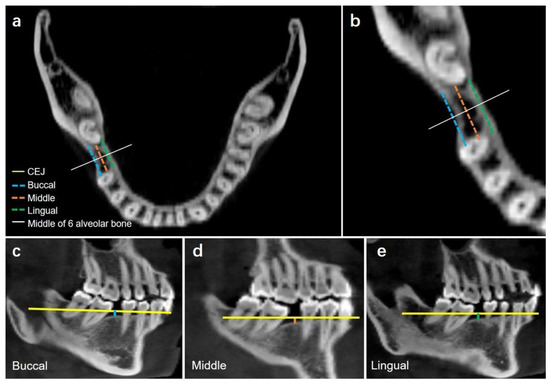

2.2.3. Alveolar Bone Loss in the Missing Tooth Region

Vertical Alveolar Bone Loss in Missing Tooth Region

Horizontal Alveolar Bone Loss in Missing Tooth Region